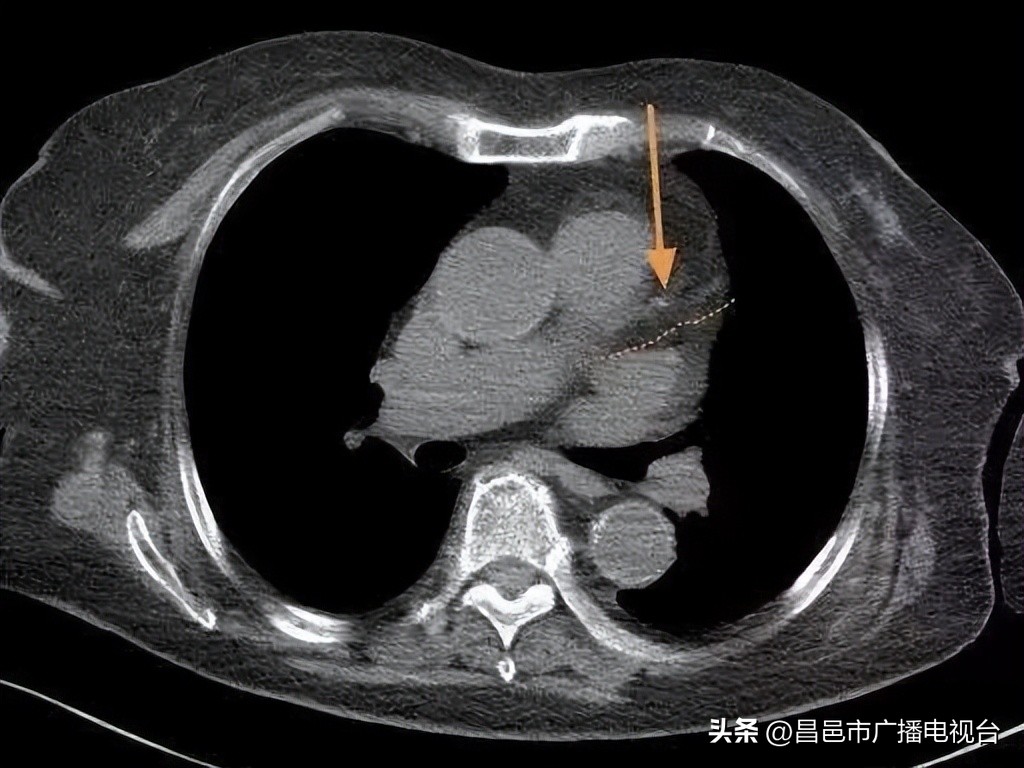

随着年龄增长,很多人会发生冠状动脉硬化,形成一些软硬斑块,引发冠心病。但这位老人只有很小的一点钙化(如图),比很多60岁的人都要好。而且检查发现,老人肺里没有结节,很干净。①

“影像科豪大夫“图